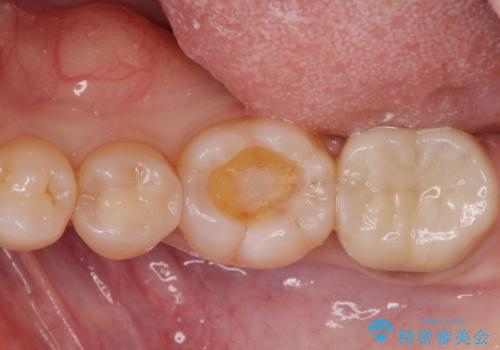

歯の噛む面が黒い。

- 歯の噛む面が黒いとのことで来院。

過去にプラスチック樹脂の治療がされており、プラスチックと歯質の隙間に汚れがたまり黒くなっていました。

劣化して黒くなりたくない、虫歯の予防がしたいとのご希望だったのでセラミックインレー(e-maxインレー)による治療を行いました。